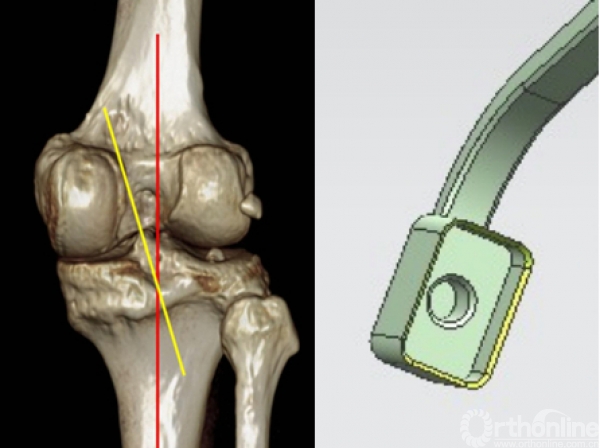

应力测试结果

a 屈曲60°侧位片

b 后向300N应力侧位片

*红线表示股骨髁后缘线

*黄线表示胫骨平台后缘线

*连续镜下观察移植韧带无明显拉伸